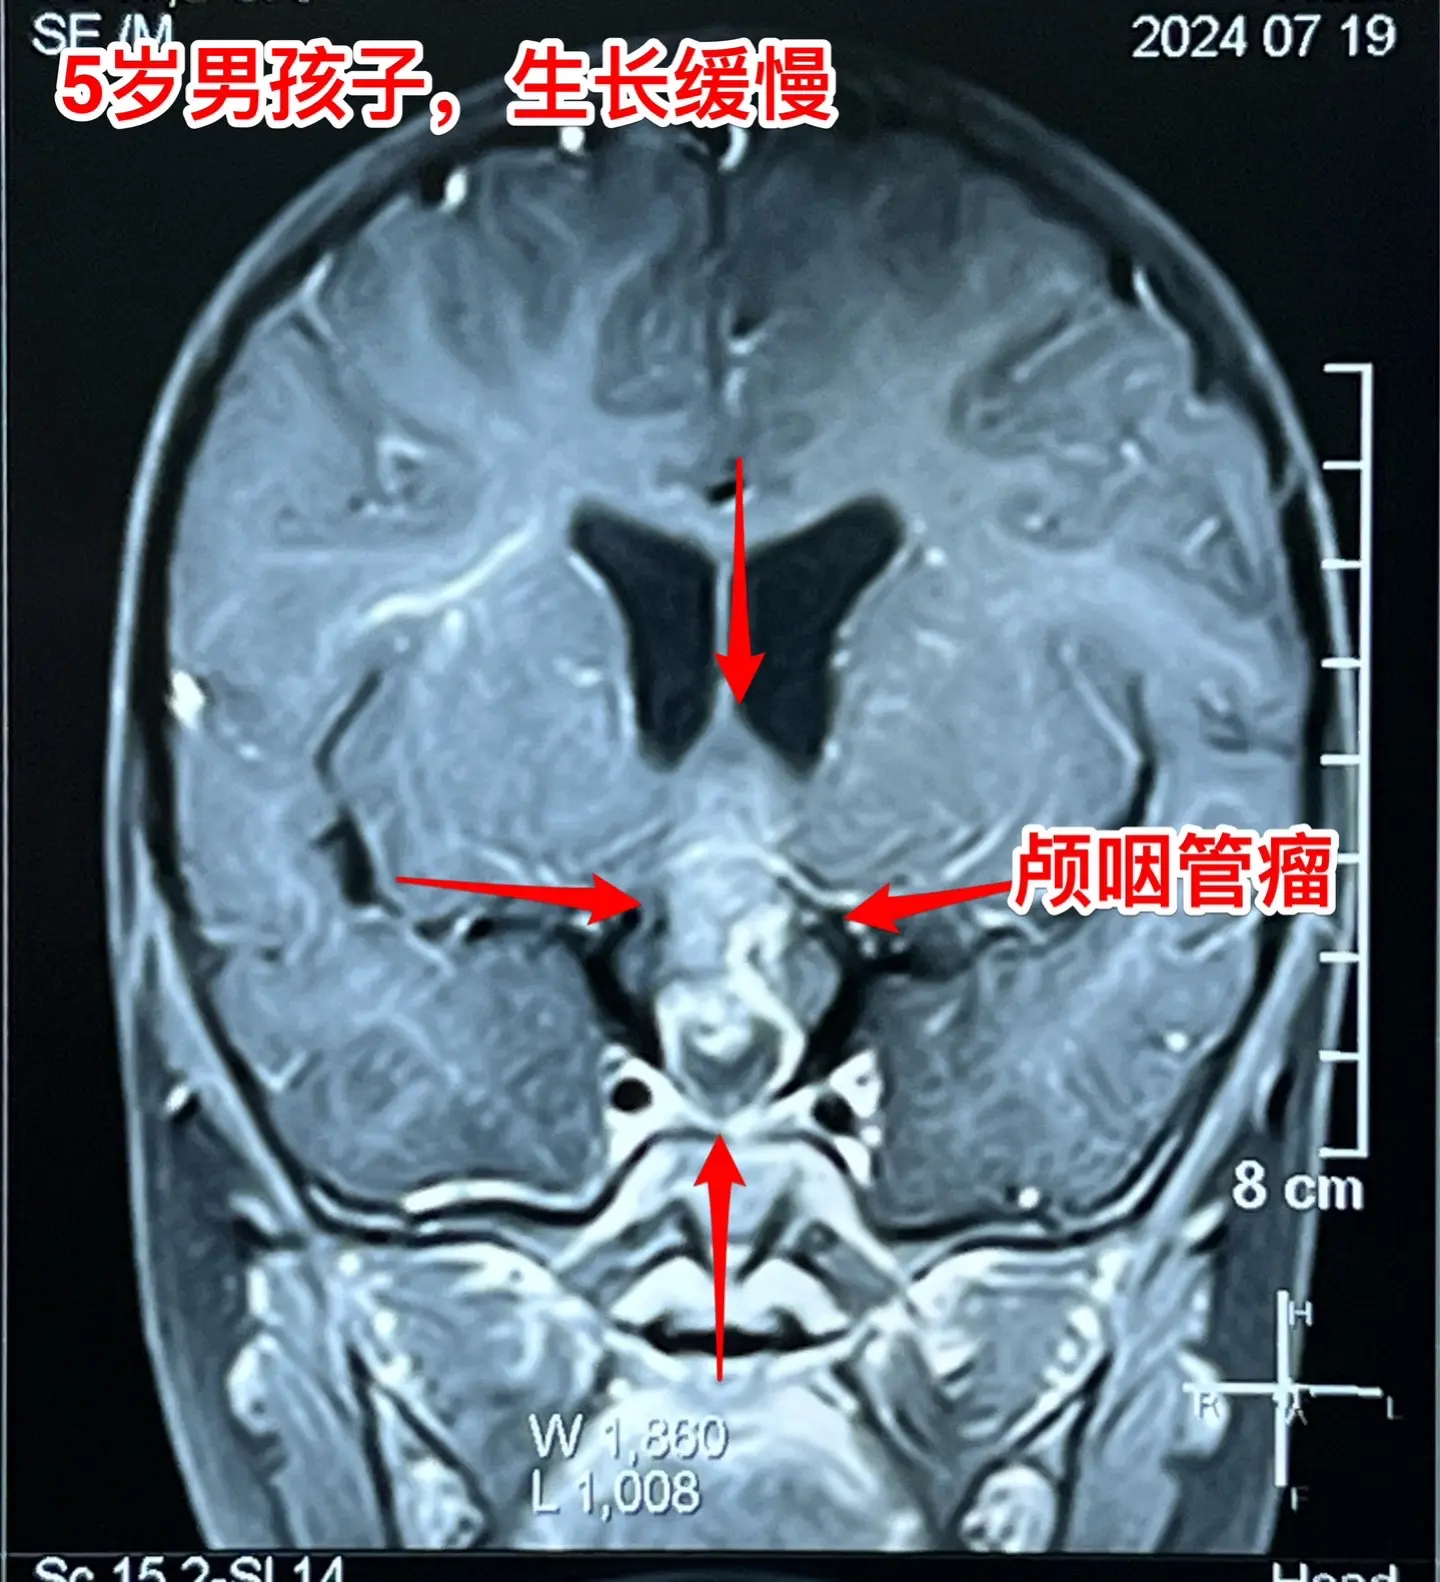

警惕小儿脑肿瘤。小孩子如果长了鞍区肿瘤,一般都会出现症状,一旦有了症状...

2024-08-28 07:49